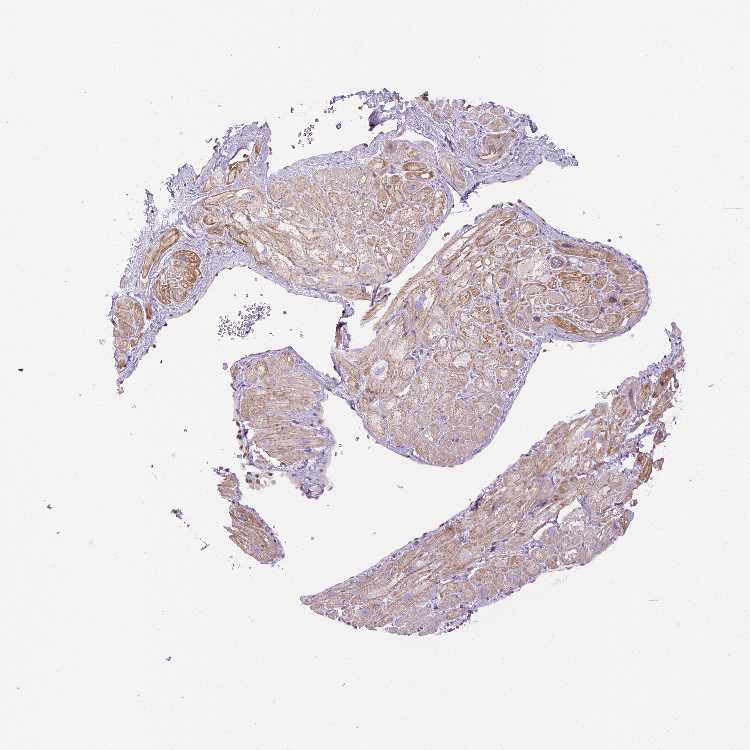

HEART MUSCLE - Antibody stainingi

Antibody staining in the annotated cell types in the current human tissue is reported as not detected, low, medium, or high, based on conventional immunohistochemistry profiling in selected tissues. This score is based on the combination of the staining intensity and fraction of stained cells.

Each image is clickable and will lead to virtual microscopy that enables deeper exploration of all samples and also displays staining intensity scores, fraction scores and subcellular localization as well as patient and tissue information for each sample.

Antibody HPA040472Antibody HPA048436Antibody CAB037302

Cardiomyocytes MediumHighNot detected